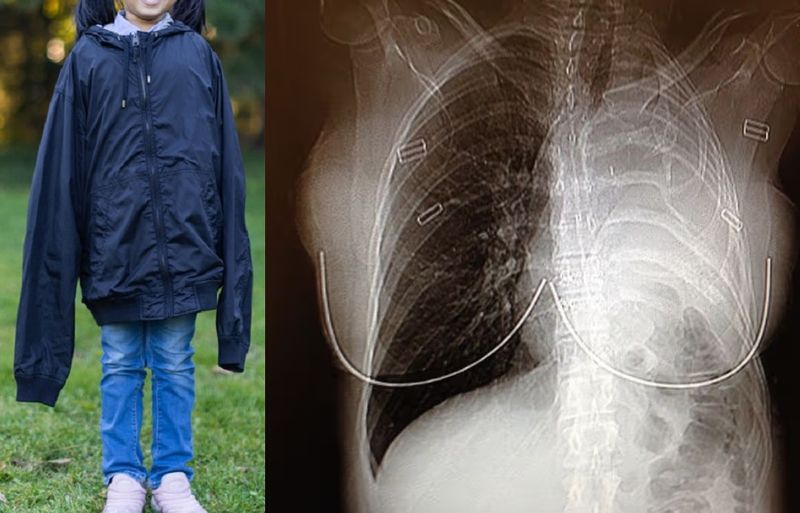

이후 병원을 찾아 CT촬영 등 정밀 검사를 받은 결과 헤더의 폐 근처에서 종양이 발견됐다.

의료진들은 석면 노출로 인해 발생하는 악성 폐암인 '악성 중피종'으로 진단했다. 수술을 받지 않을 경우 그녀의 남은 수명은 15개월에 불과했다.

이에 헤더는 보스턴의 전문의를 찾아가 왼쪽 폐와 갈비뼈 한 개, 흉막, 심장막, 횡격막 일부를 제거하는 대수술을 받았다. 수술 후에는 4차례의 온열 항암 치료와 30번의 방사선 치료를 견뎌냈다.